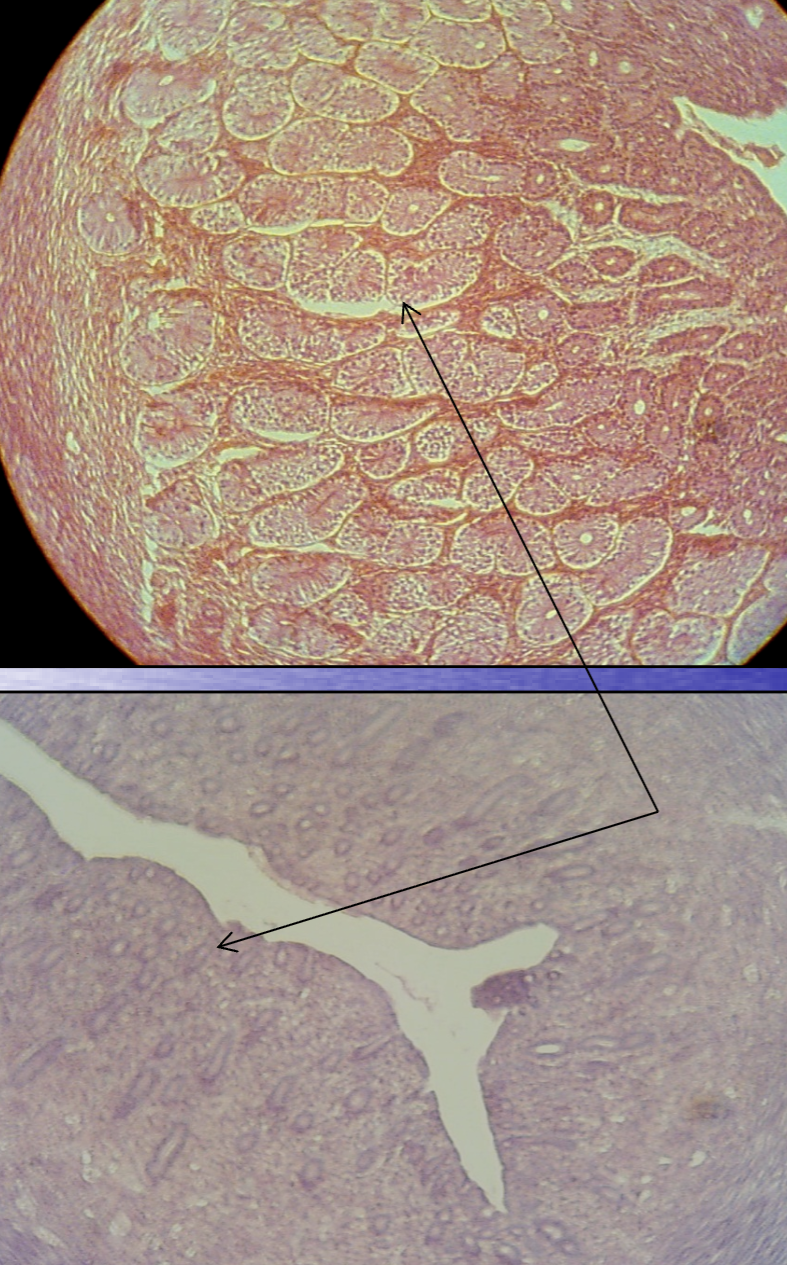

What is the structure being shown in this image?

*Hint: The ovulated follicle is transformed rapidly into this new, highly vascularized, glandular structure.

Corpus luteum

*Hint: With time, a hyaline intercellular material accumulates, and the former corpus luteum assumes the appearance of an irregular white, hyaline scar.

Corpus albicans